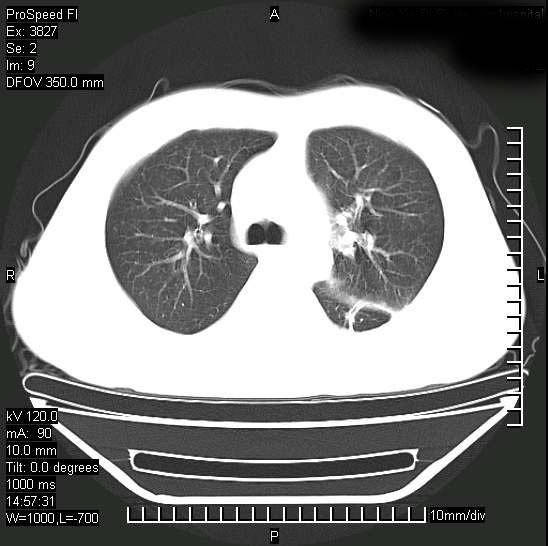

男性,一月前出现右侧肋区疼痛,较剧烈,干咳,无发热,自诉使用抗炎药后缓解,几天前又出现左侧剧烈疼痛,

发热,体温38。9,今天ct,考虑左侧包裹性脓胸,胸腔积液,右上中肺小斑片影,结核/炎症?胸水未见恶性细胞。

支持:脓胸!并双肺继发性肺结核!

左侧肺脓疡,化脓性胸膜炎(脓胸),不支持结核诊断,建议继续抗感染治疗

脓胸没问题,肺内还可见感染灶,感觉不像是结核性病变.